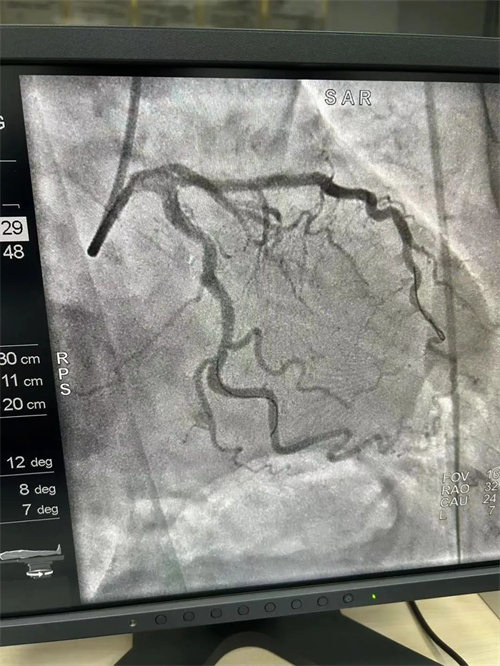

患者李大爷(化名),70岁,近半月来频繁出现胸痛、胸闷等症状,严重影响了日常生活。经过冠状动脉造影检查,李大爷被诊断为冠状动脉粥样硬化性心脏病,前降支、回旋支均达95%狭窄,需进行冠状动脉支架植入手术。经过充分的术前准备,犍为县中医医院介入诊疗中心医护团队为李大爷实施了手术。手术过程非常顺利,分别于前降支、回旋支各安置支架1枚,术后李大爷的胸痛、胸闷症状明显缓解。

![]() |

支架后